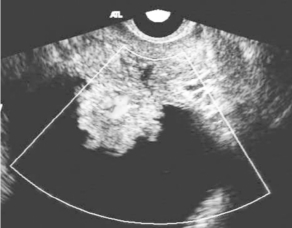

图30-3 膀胱肿瘤声像图(见彩图38)

经直肠腔内扫查膀胱壁不规则实性病变,能量多普勒可见肿瘤内部血管走行紊乱